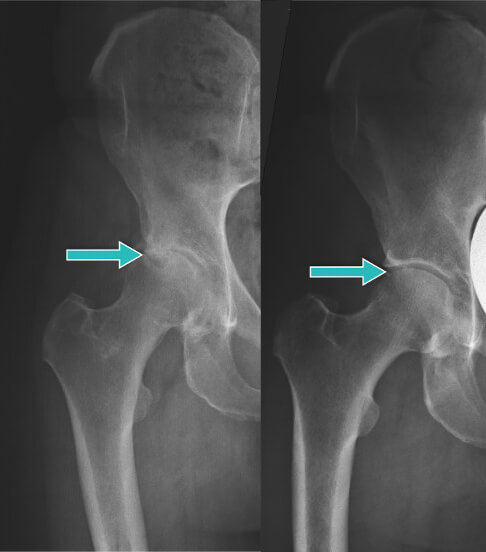

Guarda come Lidia ha curato le sue ginocchia in 7 giorni:

Ha detto: “Per molto tempo ho avuto un intenso dolore all'articolazione del ginocchio sinistro. Per questo motivo, c'erano difficoltà nel movimento. Sono andata da uno specialista, mi è stato diagnosticato un edema al femore sinistro. Si sono offerti di eseguire un'operazione al ginocchio, ma ero molto spaventata dalla procedura durante la quale si inserivano gli aghi dentro il corpo. Fortunatamente, ho incontrato Leonardo e ho iniziato ad usare Cannabis Oil appena in tempo. Dopo 3 giorni il dolore è completamente scomparso e una settimana dopo camminavo già senza dolore e ha iniziato a fare nordic walking seguendo la moda. La foto mostra il risultato dei miei progressi.”